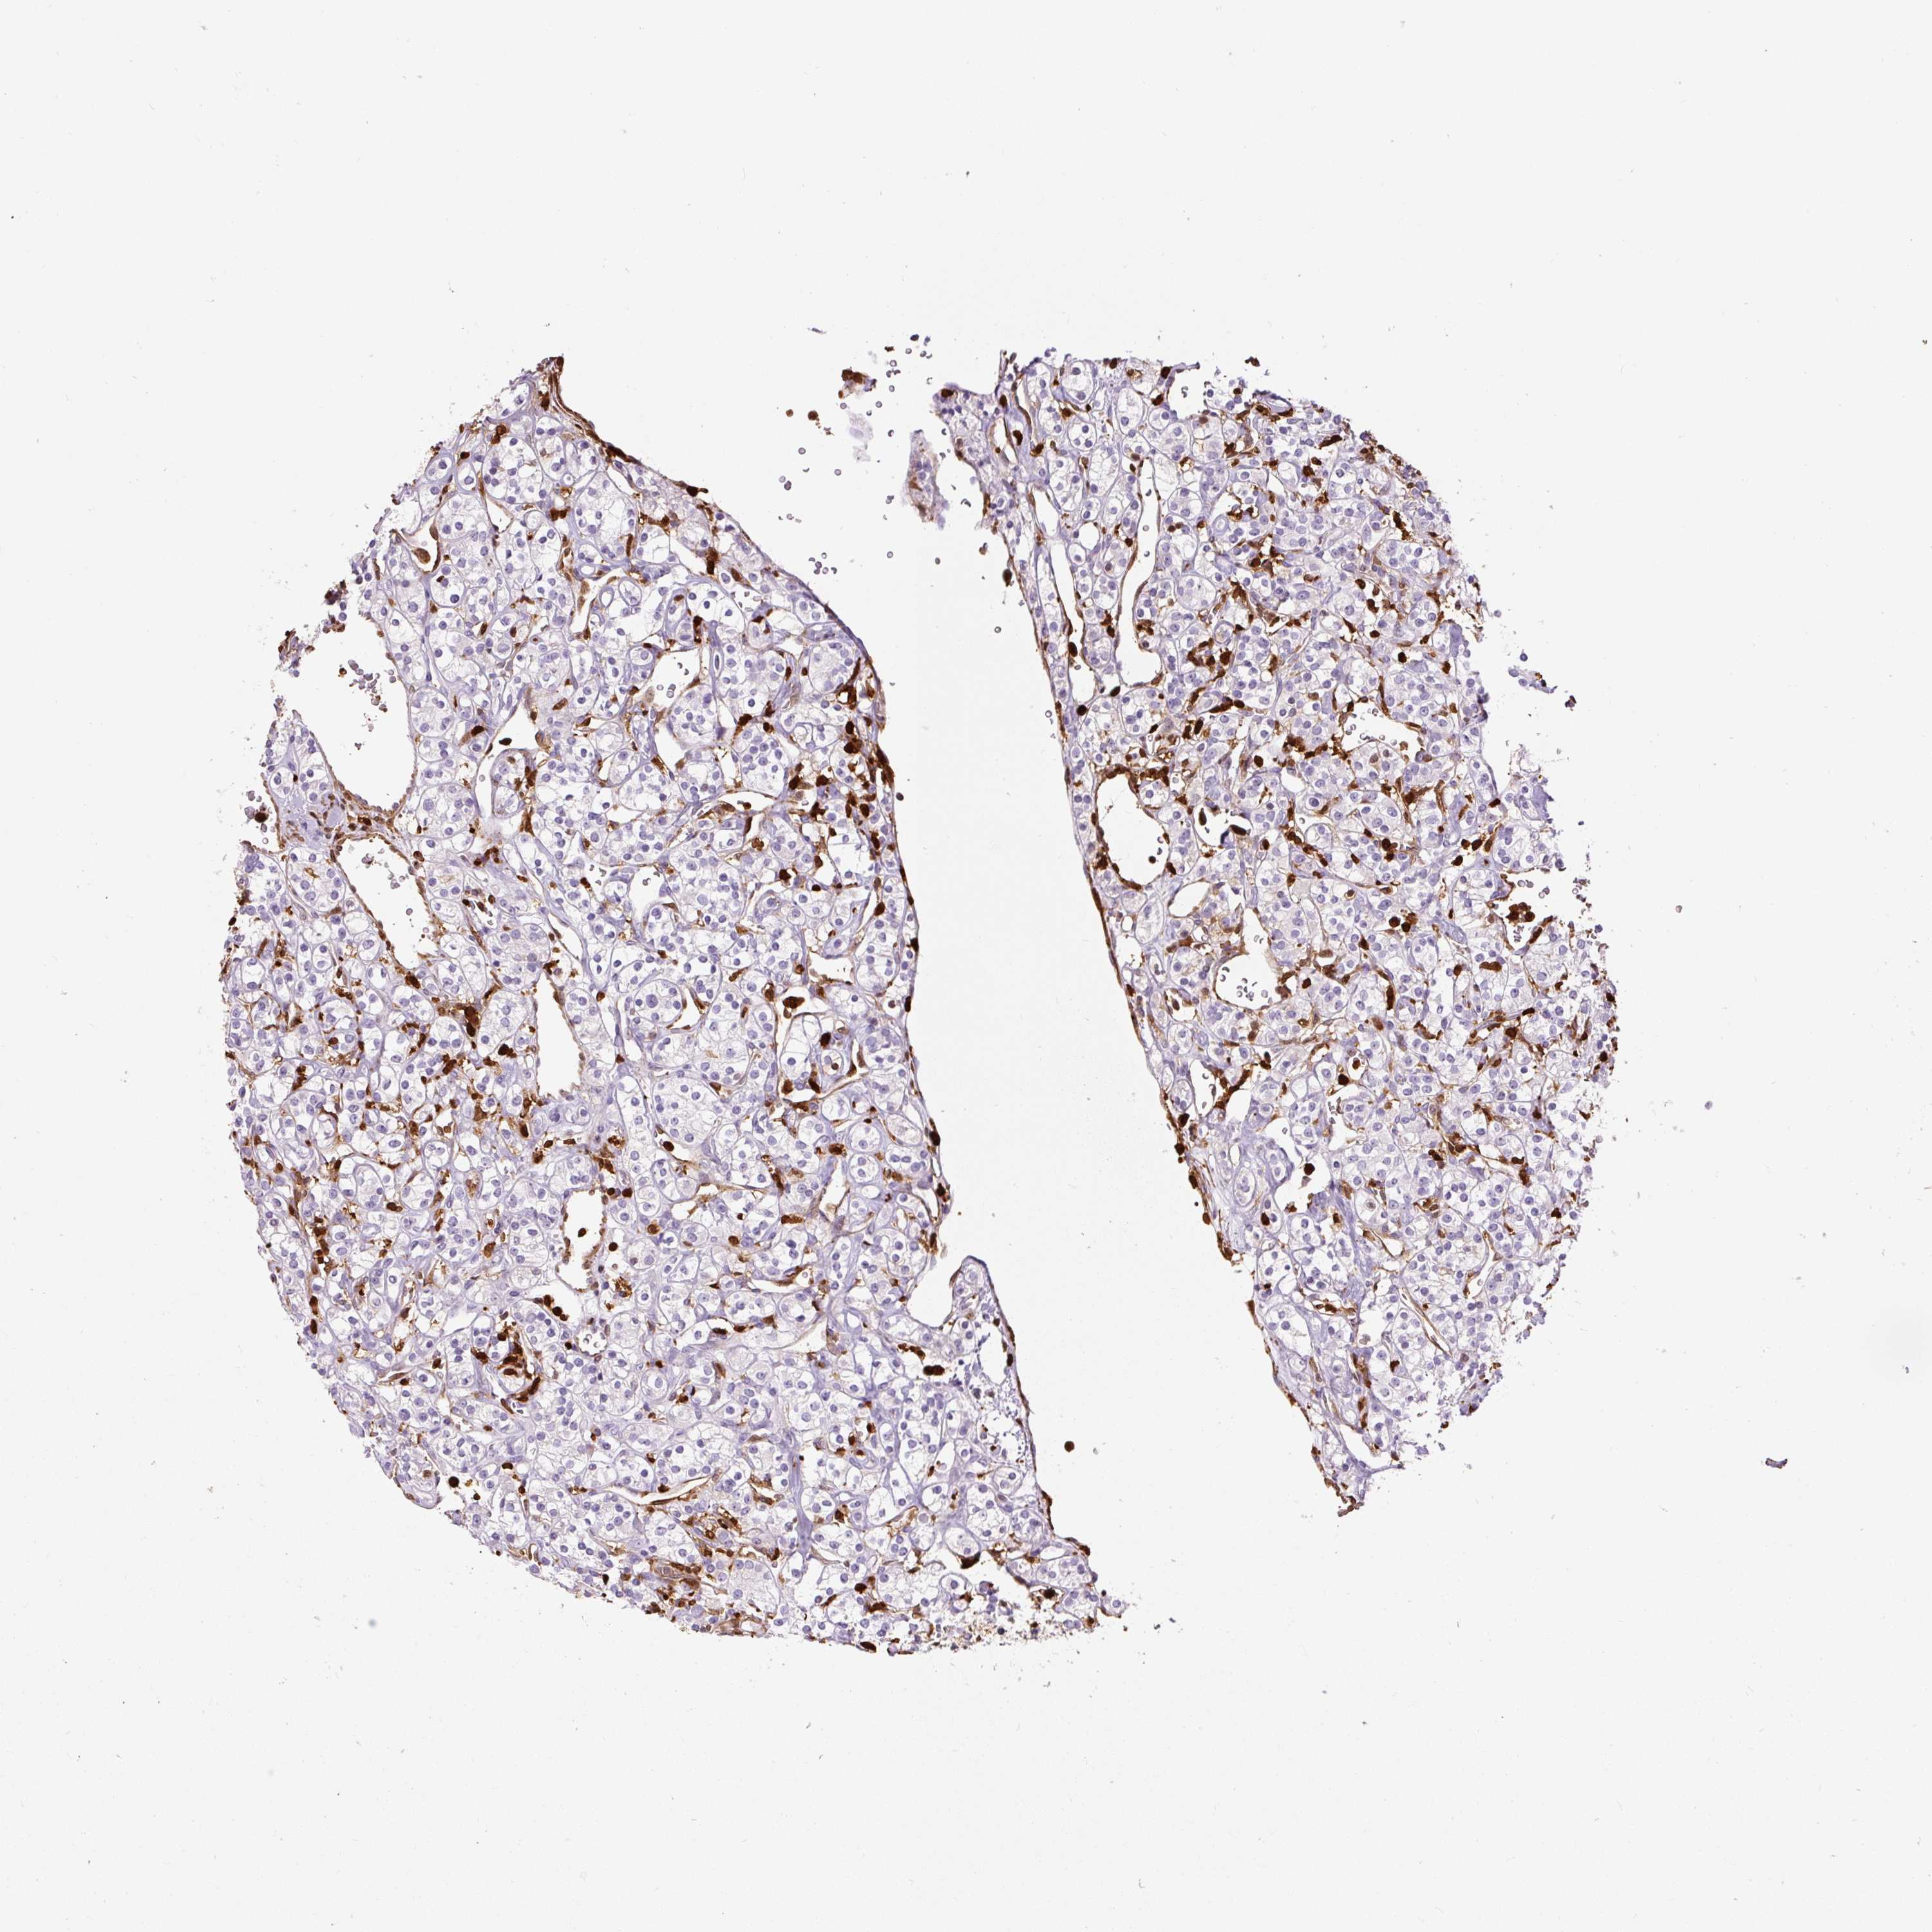

KIDNEY RENAL CLEAR CELL CARCINOMA (VALIDATION) - Interactive survival scatter ploti

The Survival Scatter plot shows the clinical status (i.e. dead or alive) for all individuals in the patient cohort, based on the same data that underlies the corresponding Kaplan-Meier plots. Patients that are alive at last time for follow-up are shown in blue and patients who have died during the study are shown in red.

The x-axis shows the expression levels (FPKM) of the investigated gene in the tumor tissue at the time of diagnosis. The y-axis shows the follow-up time after diagnosis (years). Both axes are complimented with kernel density curves demonstrating the data density over the axes. The top density plot shows the expression levels (FPKM) distribution among dead (red) and alive patients (blue). The right density plot shows the data density of the survived years of dead patients with high and low expression levels respectively, stratified using the cutoff indicated by the vertical dashed line through the Survival Scatter plot. This cutoff is automatically defined based on the FPKM cutoff that minimizes the p-score. The cutoff can be changed by dragging the vertical line or by entering a cutoff value in the square labeled "Current cut-off".

Under the Survival Scatter plot the p-score landscape (black curve; left axis) is shown together with dead median separation (red curve; right axis). Dead median separation is the difference in median mRNA expression between patients who have died with high and low expression, respectively. It is calculated as follows: median FPKM expression of dead patients with high expression - median FPKM expression of dead patients with low expression. This is intended to aid the user in visually exploring custom cutoffs and the associated p-scores and dead median separation.

Individual patient data is displayed and can be filtered by clicking on one or more of the category buttons on the top of the page. Categories describing expression level and patient information include: high, low, alive, dead, female, male and tumor stages. The scale of the x-axis can be toggled between linear and log-scale by clicking on the "x log" button. Mouse-over function shows TCGA ID, patient information and mRNA expression (FPKM) for each patient.

& Survival analysisi

Kaplan-Meier plots summarize results from analysis of correlation between mRNA expression level and patient survival. Patients were divided based on level of expression into one of the two groups "low" (under cut off) or "high" (over cut off). X-axis shows time for survival (years) and y-axis shows the probability of survival, where 1.0 corresponds to 100 percent.

S100A4 is not prognostic in Kidney Renal Clear Cell Carcinoma (validation)

: 108.1

Average pTPM 173.2

Number of samples 100